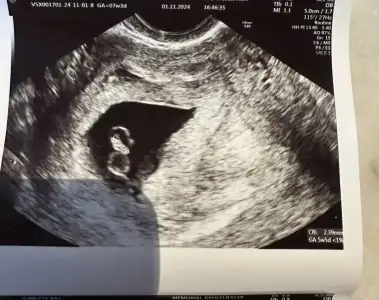

Kızlar güzel haberler alamadım malesef, geçen hafta gelişimi bir hafta geriden geliyordu. Ve kalp atışını duymamıştık. 6+4 tük. Bu hafta 7+3 ken geldim. Bebeğin kalp atışı duyuldu ama yavaş dedi doktor. 100 ün altında. Ve bebeğin üstünde ikinci bir yolk sac var sandı önce sonra bebek sağlıksız olduğu için su kesesi oluşabiliyor üstünde ona benziyor dedi. Boyunu ölçerken de tam boyunu almadı sanki doktor. 2.39 mm çıktı. Geçen hafta 2.7 çıkmıştı. Küçülemez herhalde. Daha önce başınıza böyle bir şey geldi mi? Haftaya belli olacak her şey.